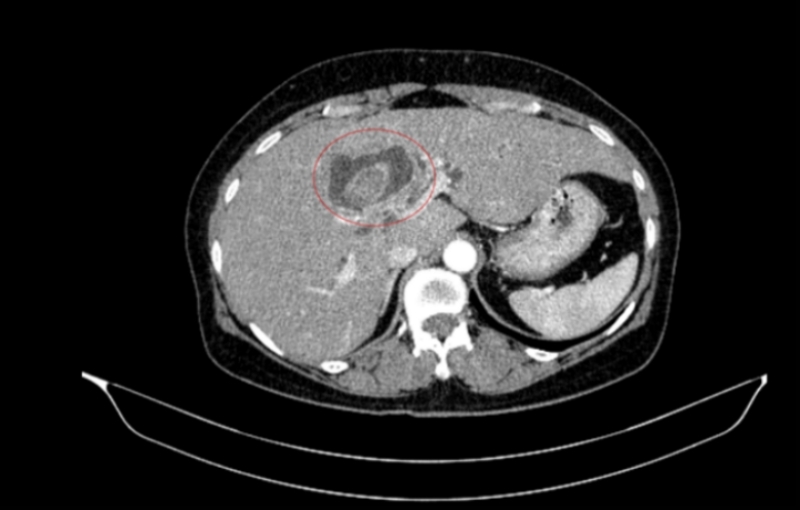

Hình ảnh sỏi đường mật tạo ổ áp xe gan - đường mật gan trái (vòng tròn màu đỏ).

Một phụ nữ 59 tuổi được các bác sĩ Trung tâm Y học hạt nhân và Ung bướu, Bệnh viện Bạch Mai, tiếp nhận trong tình trạng vàng da, ngứa và đau vùng hạ sườn phải kéo dài. Kết quả chẩn đoán hình ảnh ban đầu ghi nhận tổn thương đường mật trong gan kèm sỏi và giãn đường mật.

Sau hội chẩn đa chuyên khoa, các bác sĩ xác định bệnh nhân mắc đồng thời hai ung thư nguyên phát, thay vì một khối u di căn. Cụ thể, ung thư đại tràng phải ở giai đoạn sớm, chưa di căn hạch, trong khi ung thư đường mật trong gan đã ở giai đoạn tiến triển, có xâm lấn và di căn hạch.